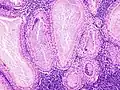

The appearance of this tumor under the microscope is unique. There are cystic spaces surrounded by two uniform rows of oncocytes, which are epithelial cells with abundant, granular, eosinophilic cytoplasm.[7] The cystic spaces have epithelium referred to as papillary infoldings that protrude into them. Additionally, the epithelium has lymphoid stroma with germinal center formation.